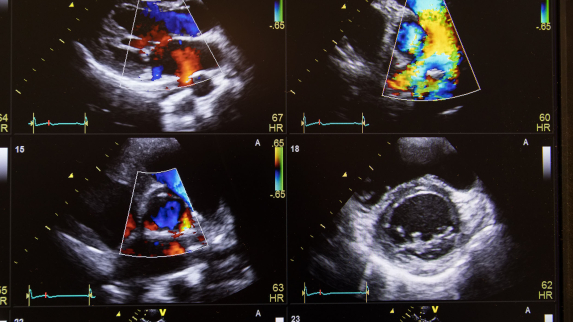

When hospitalized patients struggle to breathe, doctors typically reach for their stethoscopes, but results from a Rutgers and RWJBarnabas Health clinical study in JAMA Network Open suggest they should diagnose the problem with portable ultrasounds instead.

The study found initial exams with portable ultrasounds led to better diagnoses, shorter hospital stays and big cost savings. However, the findings revealed a need for additional training and workflow integration to help clinicians transition from traditional tools to this promising new technology.

“The study clearly shows that ultrasound is the superior diagnostic technology, even for long-time stethoscope users who get a few hours of ultrasound training,” said senior study author Partho Sengupta, Henry Rutgers professor and chief of cardiology at Rutgers Robert Wood Johnson Medical School (RWJMS), chief of cardiology at Robert Wood Johnson University Hospital (RWJUH) and member of the RWJBarnabas Health Medical Group. To read the full story.